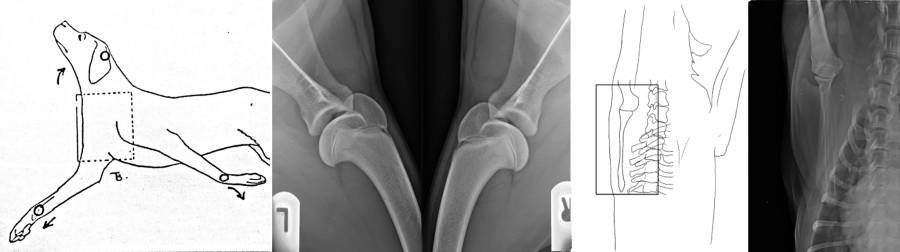

- Lagerung Extremitäten

- Vergleichende Aufnahmen: z.B. rechtes und linkes Knie

- Ausnahmen: frisches Trauma, post-OP

- Grundbilderpaar wenn nötig: 2 Ebenen

- Richtungsmarken distal anbringen

Röntgen Hüfte

Röntgen Knie

Röntgen prä-OP TPLO